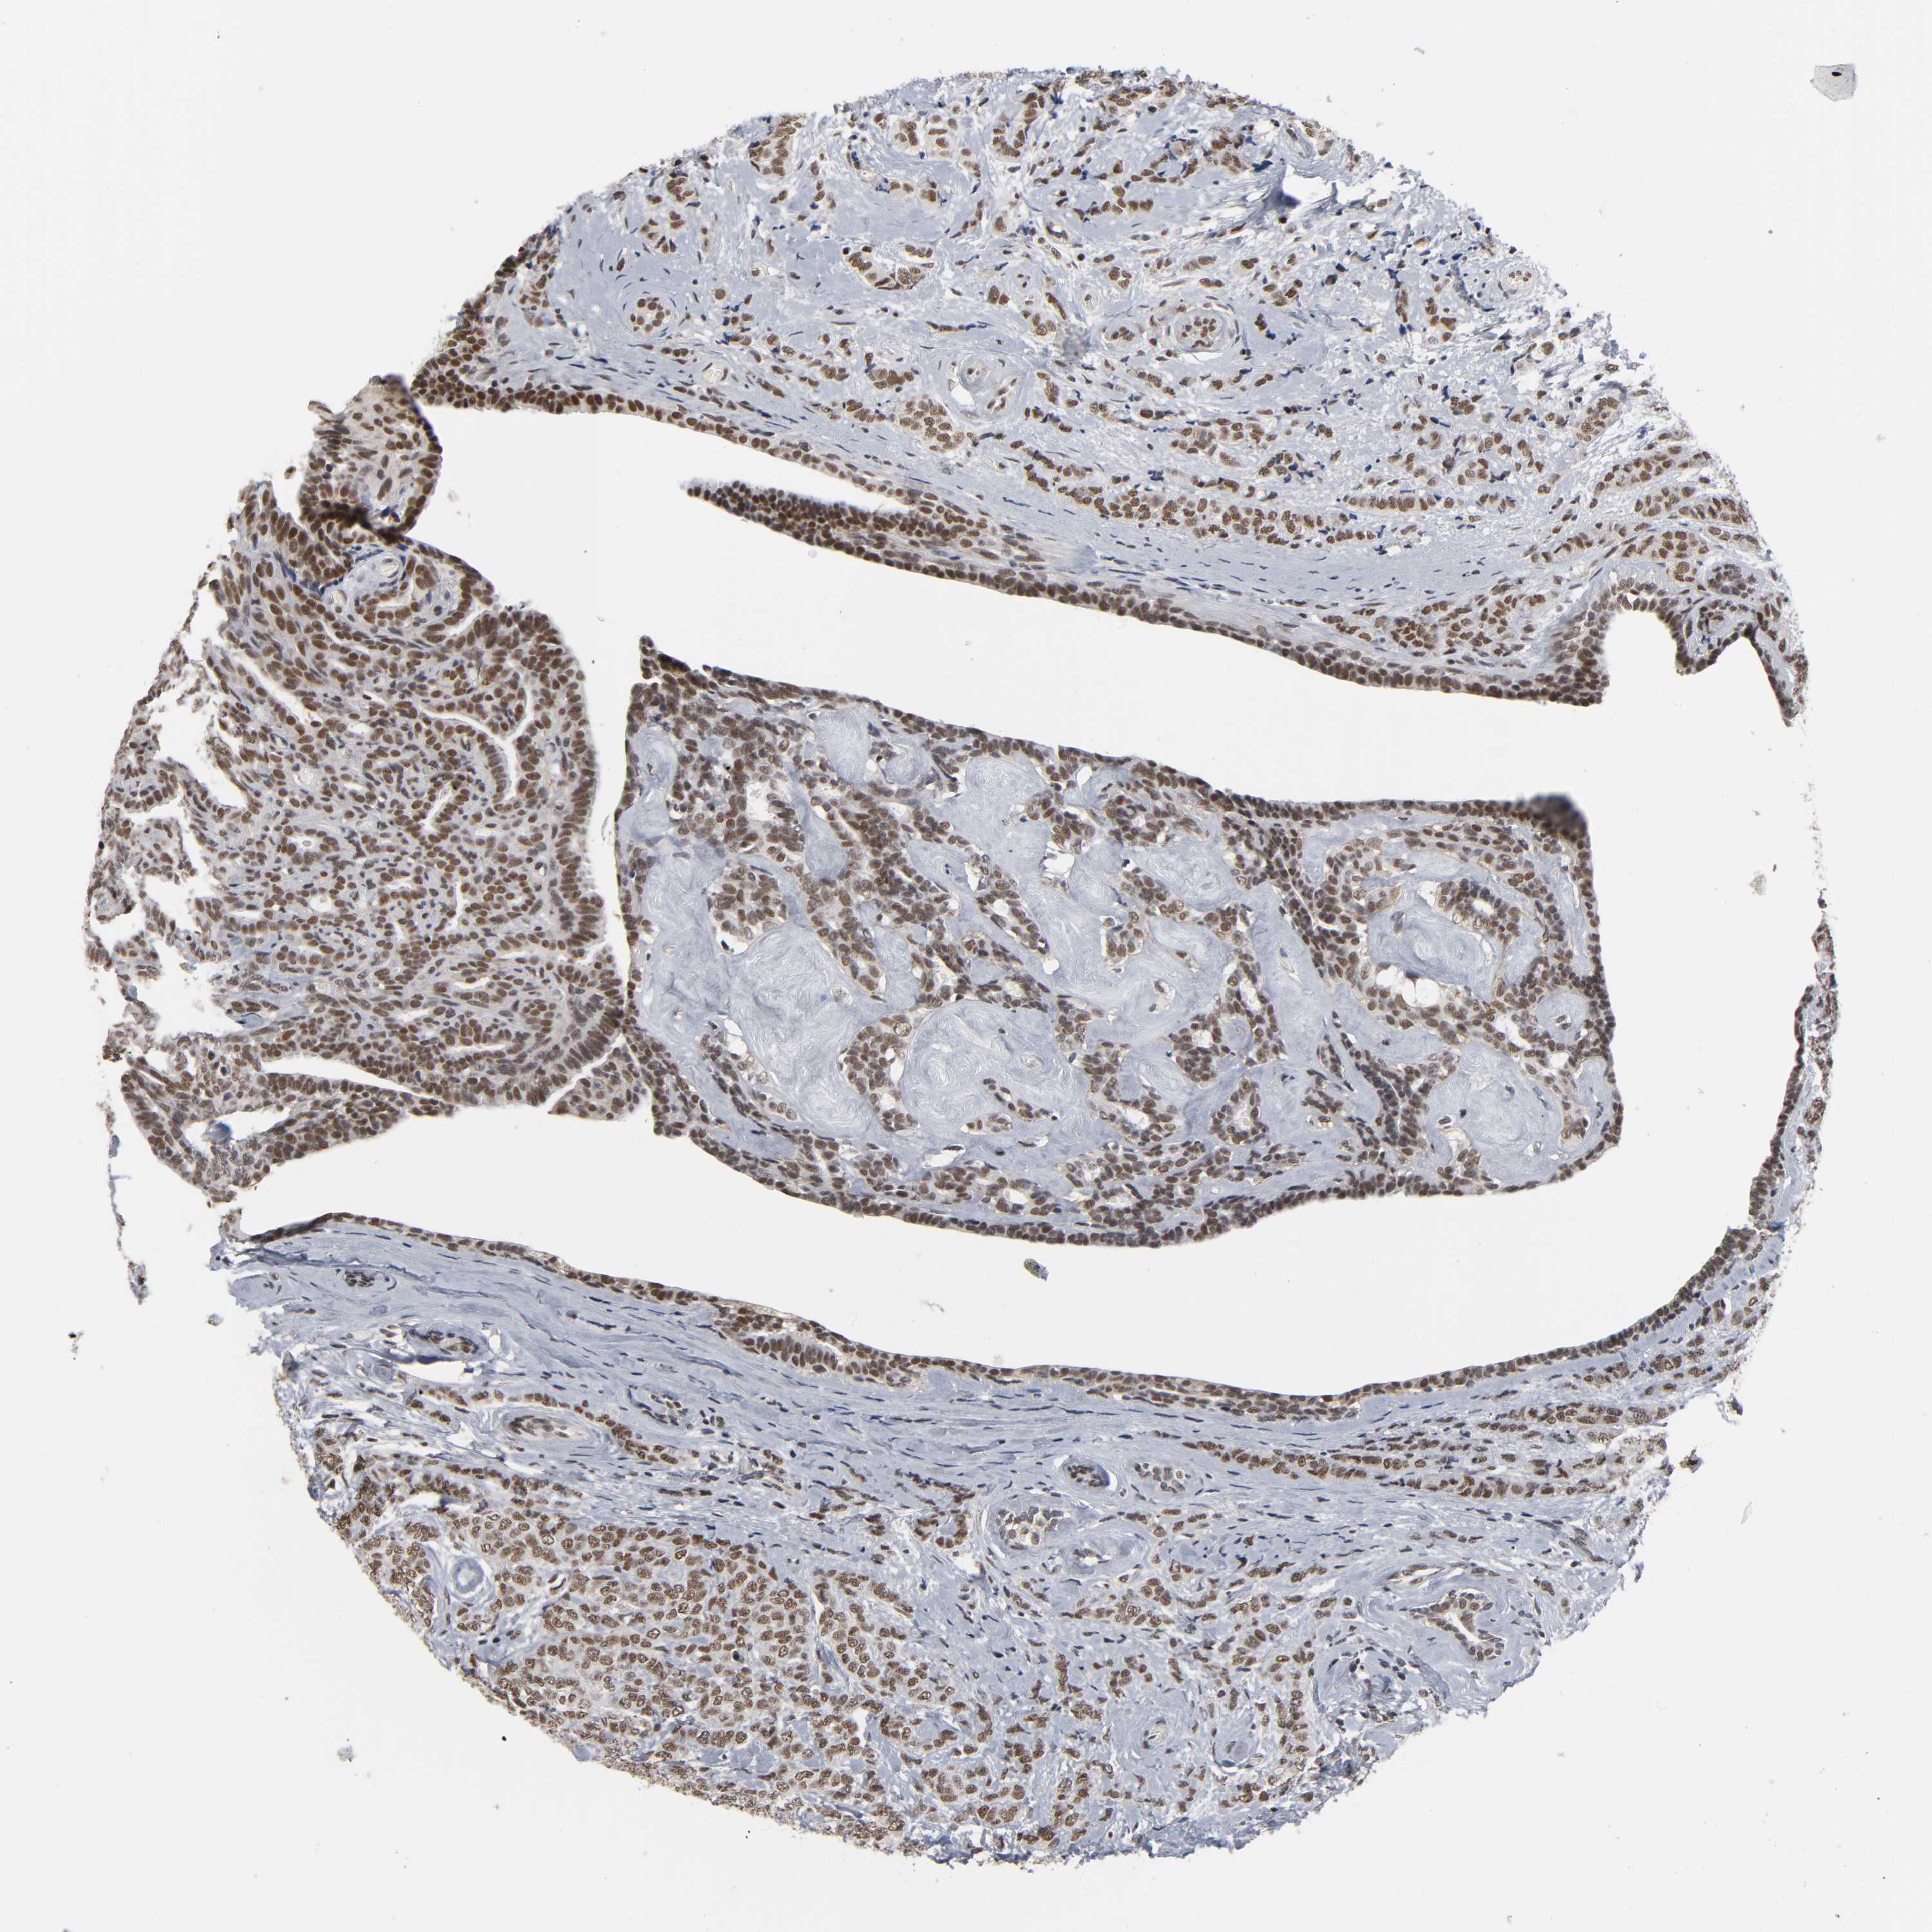

CANCER BREAST CANCER Show tissue menu

BRCA TCGA BRCA VALIDATION PROTEIN EXPRESSION